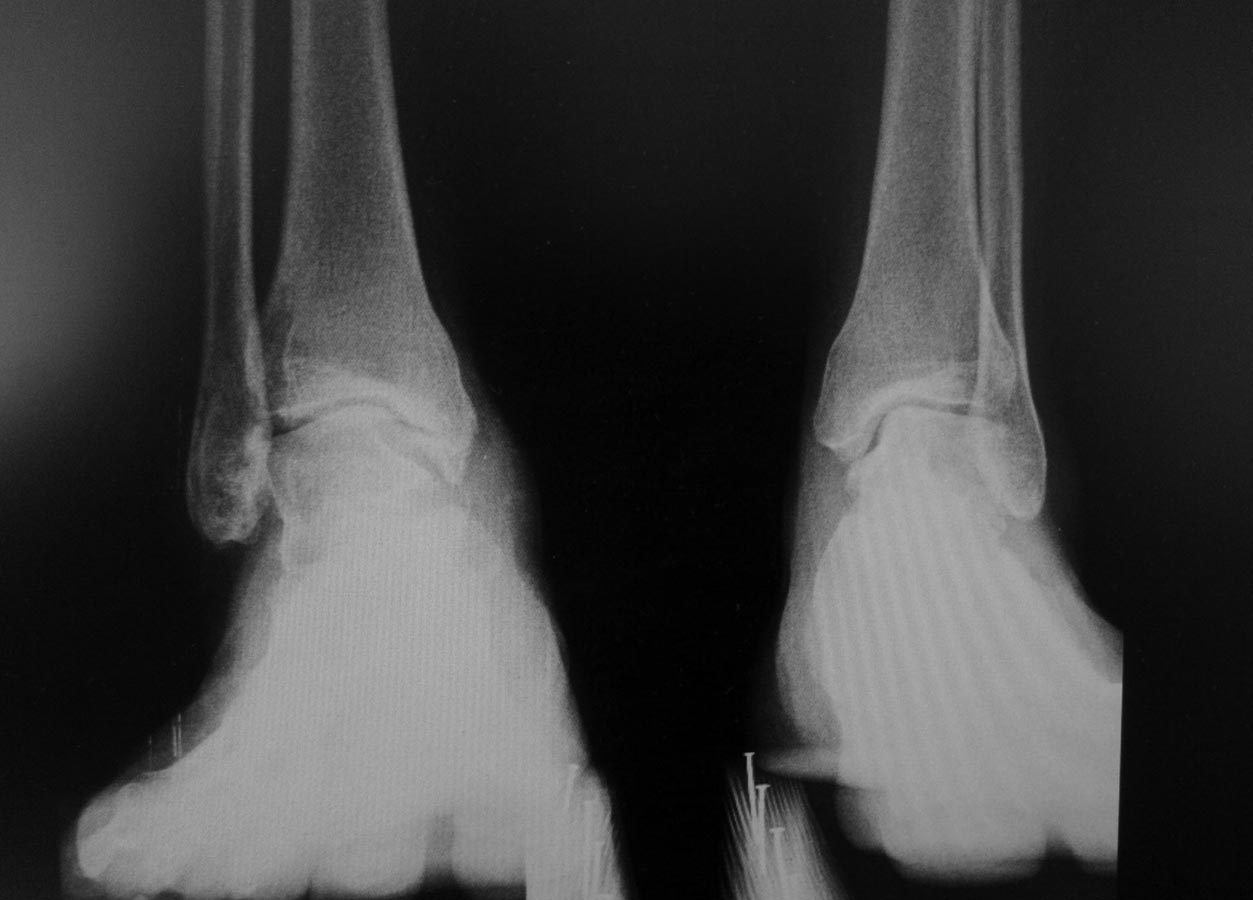

Деформация голеностопного сустава

Добрый день! Обратилась женщина 1975 г.р с болями в правом голеностопном суставе.

Случай обсуждался здесь. Только сейчас появилась возможность сделать Rg с нагрузкой. За это время (с апреля 2016 г.) усилились боли и деформация.Какова тактика лечения на ваш взгляд в данном случае?

Уважаемые, а не была ли тут травма в/3 малоберцовки (я имею в виду надсиндесмозную травму голеностопного сустава) с разрывом синдесмоза. Возможно такой вариант: пробовать востановить целостность синдесмоза (может быть даже с остеотомией для востановления длинны м/берцовой кости) c жесткой фиксацией, и втом случае если устранится подвывих и будет стабилен сустав на этом и успокоится. Благодарю за внимание.

Неестественная форма таранной кости позволяет предположить, чт травма была на фоне уже существующей патологии. Хотелось бы получить ответ на ряд вопросов: 1. Не было ли проблем со стопой с раннего детства? 2. Не было ли пареза малоберцового нерва, "шлепающей" стопы"? 3. Нет ли гипотрофии икроножной мышцы? 4. Нет ли внешних признаков стопы Фридрейха?В любом случае наверное предпочтителен артродез, но хотелось бы точнее определиться с диагнозом, кроме артроза.

Конечно нужно смотреть клинически, но по рентгенограмме можно предположить передний импиджмент. Возможно ремоделирование переднего края большеберцовой облегчит страдания пациентки.